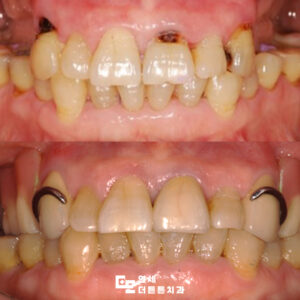

망월사역치과 변색된 아래 앞니 브릿지 수복

망월사역치과 변색된 아래 앞니 브릿지 수복 치아는 음식물을 씹고 끊는 저작기능 외에도 외모에 중요한 영향을 미치며 특히 앞니는 잘 드러나기 때문에 색상이나 배열이 좋지 않으면 타인에게 부정적인 인상을 줄 수 있습니다. ​ 이에 따라 보철치료가 필요할 때가 있는데 이를 고려하기 전에는 반드시 확인해야 할 중요한 사항들이 몇 가지 있습니다. ​ 더보기…